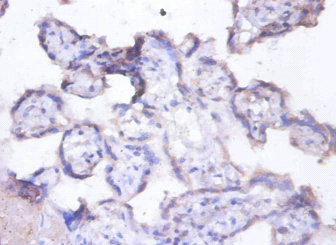

Immunohistochemistry of paraffin-embedded human placenta tissue using CSB-PA07974A0Rb at dilution of 1:100